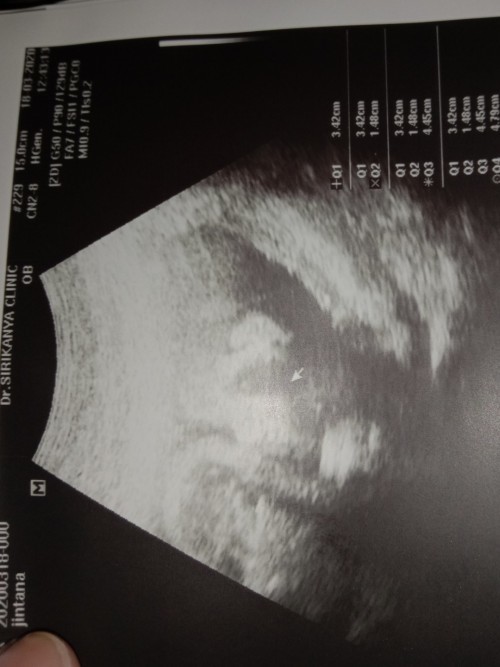

ยังไม่รู้เพศเลยค่ะ กำหนดคลอด 9 มกราคม 2564🥰🥰